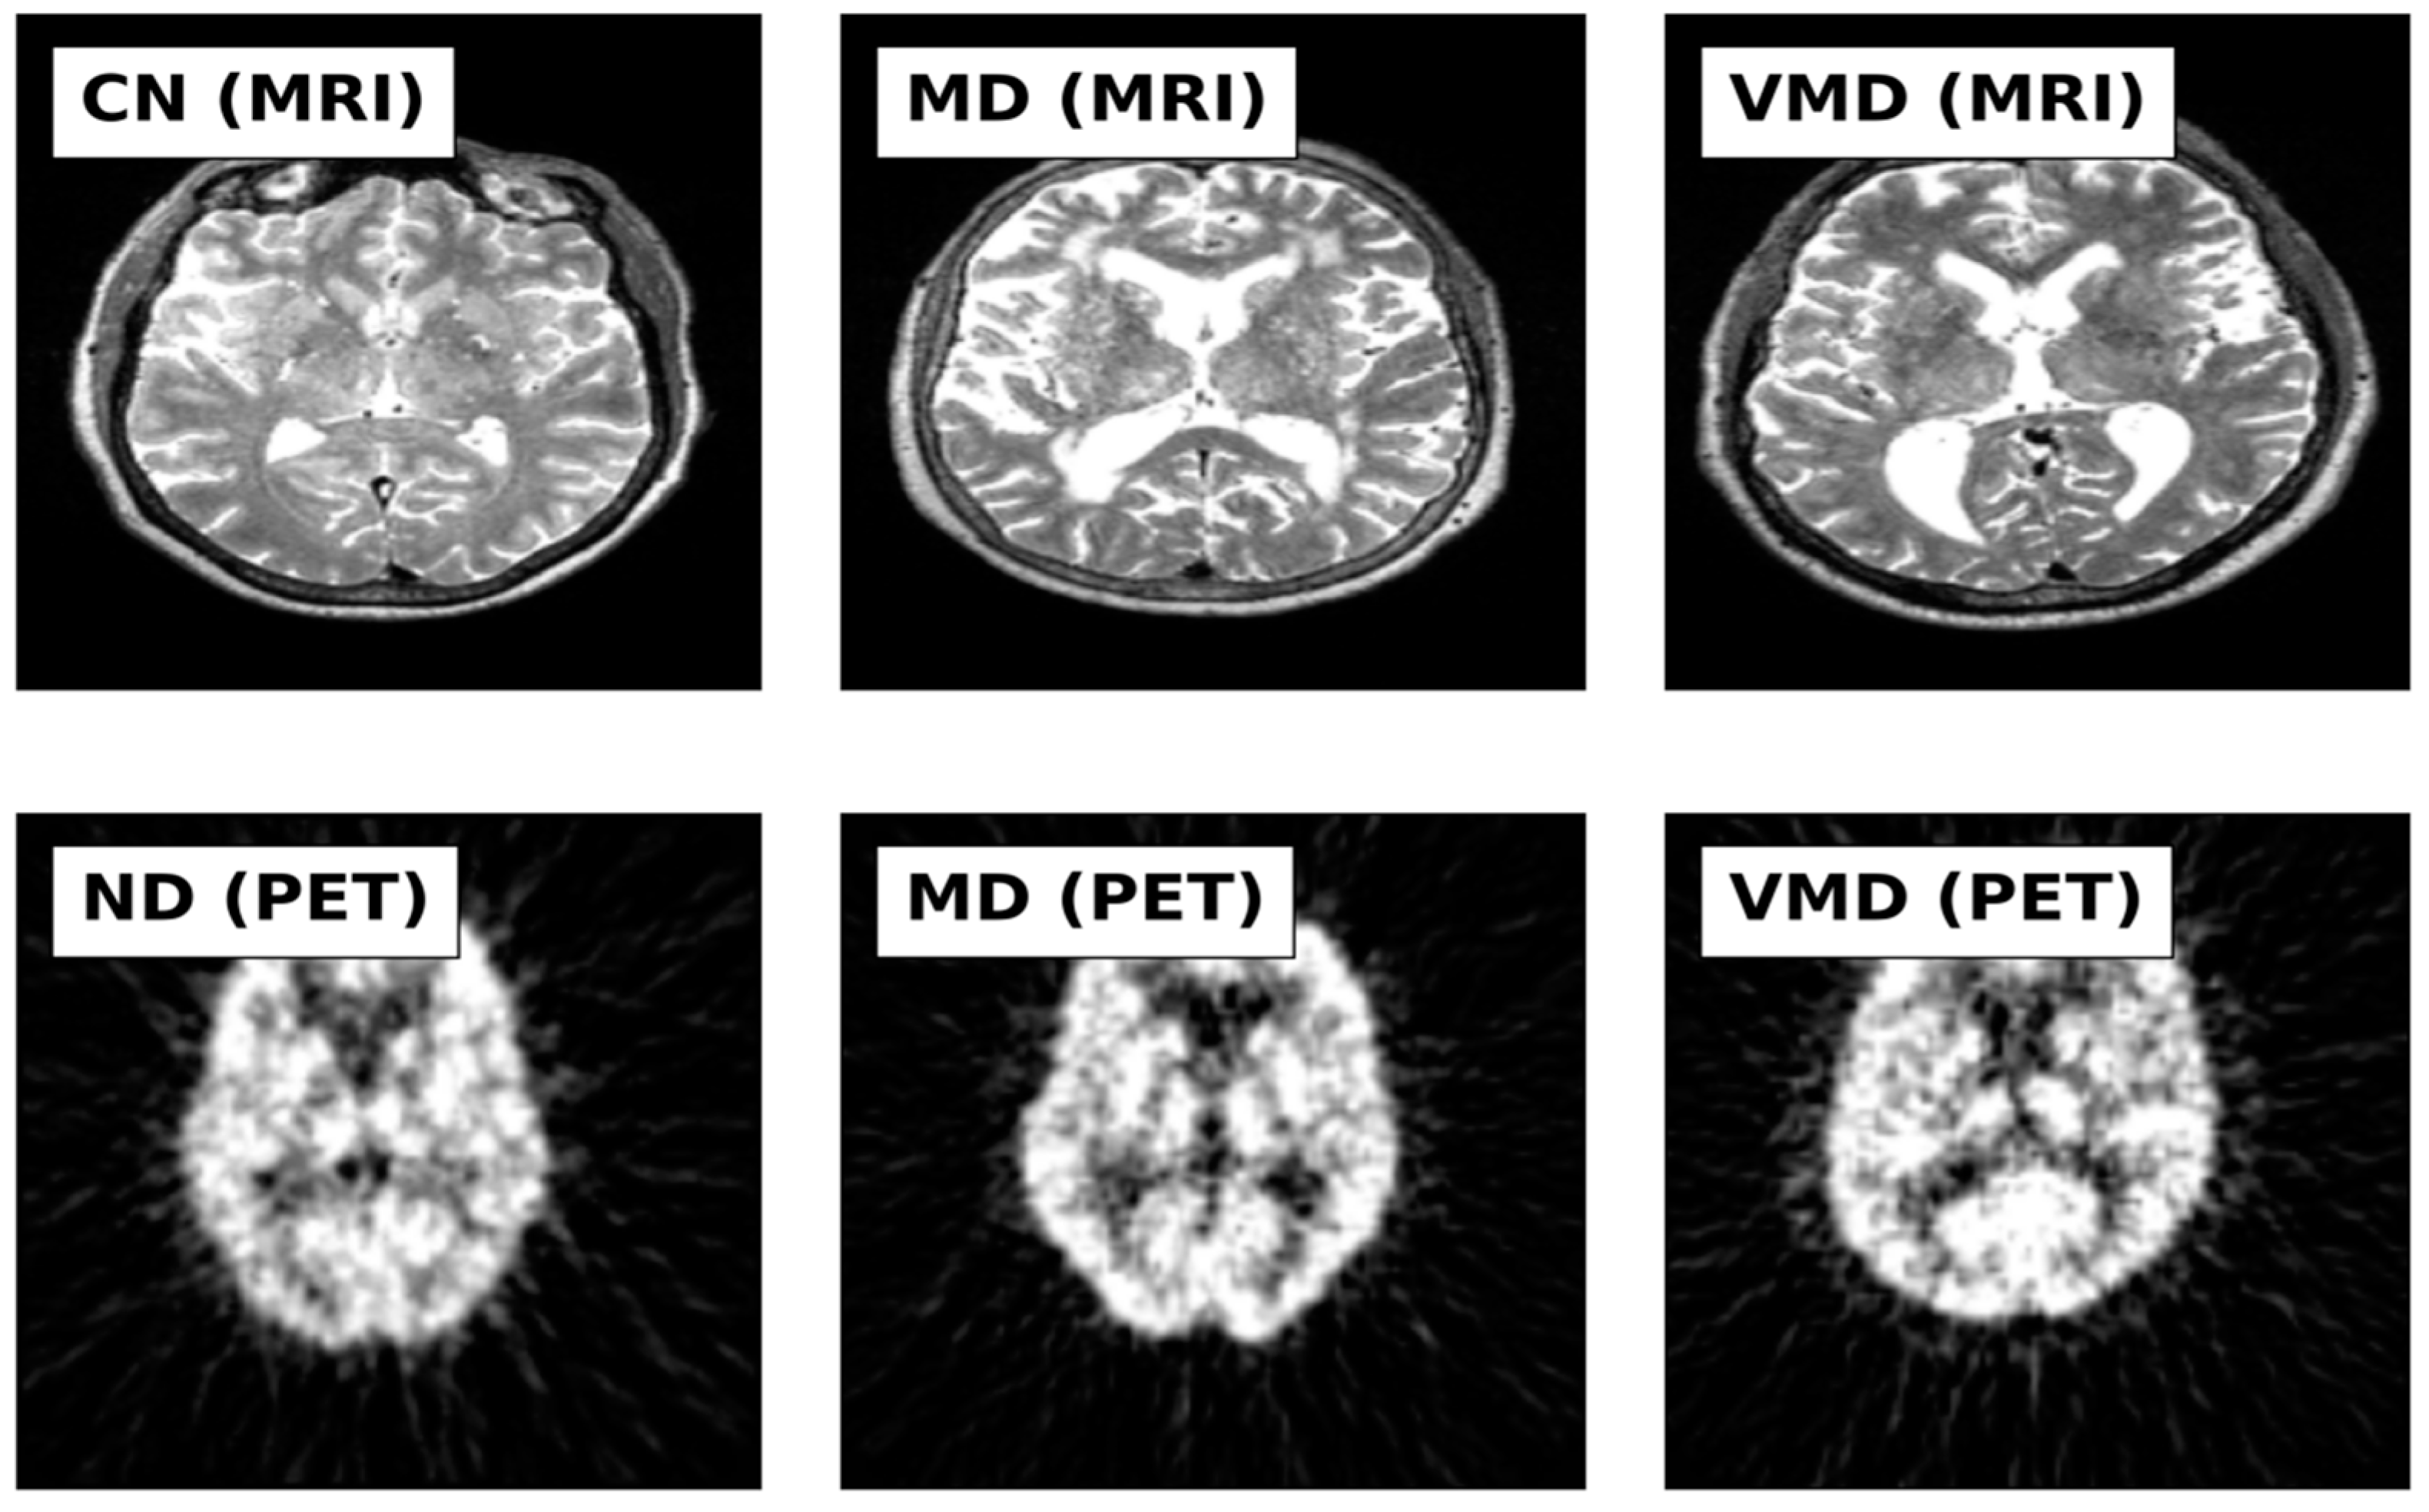

2.1. Datasets